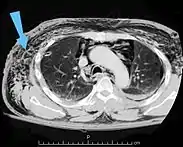

![]() | |

| An abdominal CT scan of a patient with subcutaneous emphysema (arrows) | |